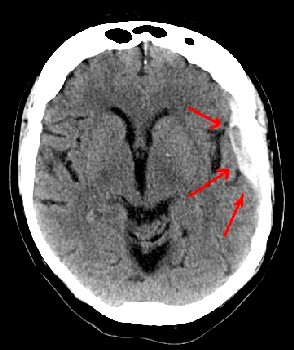

Photo: Lucian Monfils

A Subdermal Hematoma (Bleeding Under the Skull)

The first problem the surgeon faced when healing a wound of the skull was removing any blood (viscous or dried) sitting on the dura mater. This was true whether the skull was trepanned or not. (Keep in mind that one of the reasons for trepanning was to give vent to blood which had been trapped under the skull.)